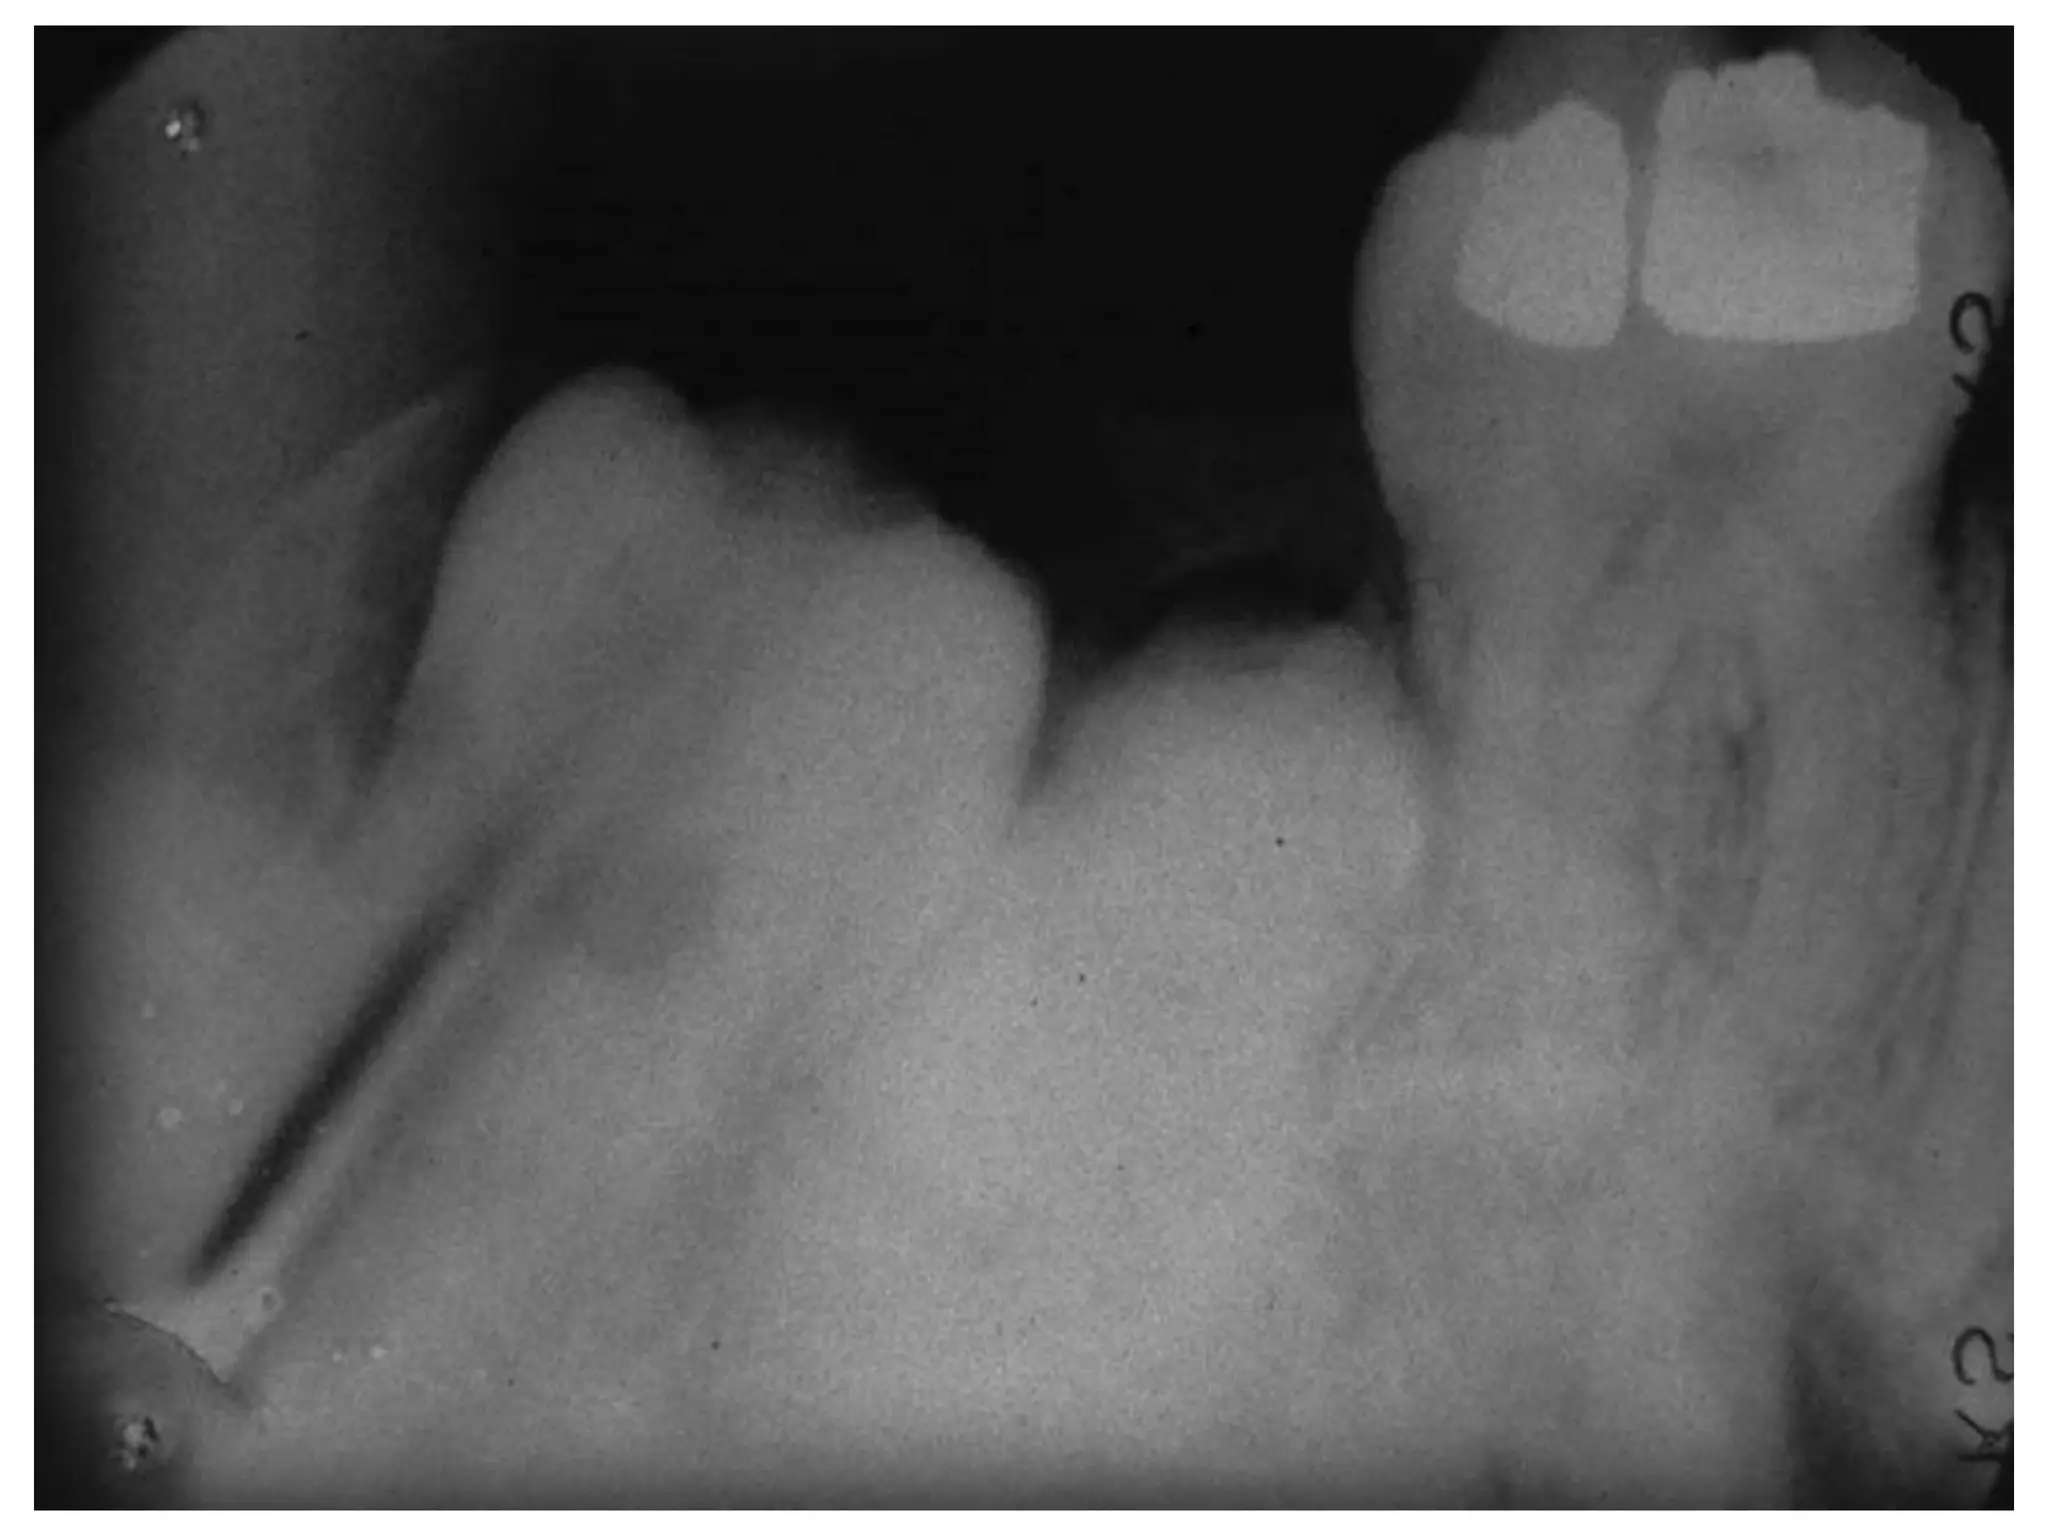

U raêng (Odontoma)

 U do raêng thöôøng gaëp nhaát.

 Khoâng phaûi taân sinh thaät söï , ñöôïc coi laø moät

dò daïng phaùt trieån (hamartoma).

 Coù 2 loaïi:

 Keát hôïp: goàm nhieàu caáu truùc nhoû gioáng raêng.

 Phöùc hôïp: laø moät khoái men vaø ngaø, khoâng mang

hình thaùi giaûi phaãu cuûa raêng.

U raêng

X quang:

 Sôùm: thaáu quang, ñöôøng vieàn roõ, nhaün.

 Muoän: caûn quang roõ.

 Daïng keát hôïp cho thaáy hình daïng raêng roõ

raøng trong khi daïng phöùc hôïp laø moät khoái caûn

quang ñoàng nhaát khoâng coù hình daïng raêng.

Giaûi phaãu beänh:

 U raêng keát hôïp (compound odontoma) goàm

men, ngaø vaø xeâ maêng saép xeáp thaønh hình

daïng raêng.

 U raêng phöùc hôïp (complex odontoma) goàm

men, ngaø vaø xeâ maêng nhöng saép xeáp ngaãu

nhieân, khoâng mang hình thaùi giaûi phaãu cuûa

moät raêng.